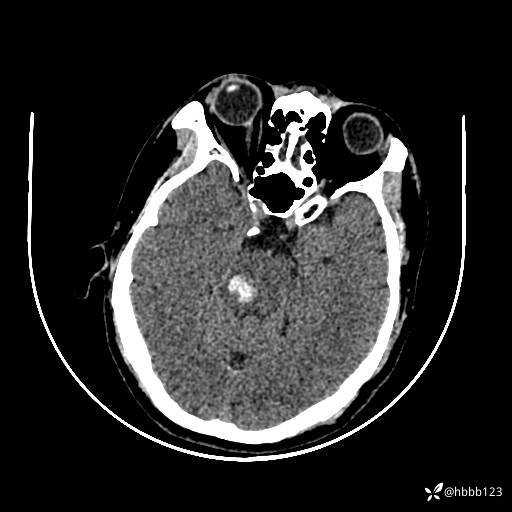

患者男,51岁。

简要病史:患者自述于1周前至某人民医院发现脑干肿瘤(具体不详),为求进一步诊断至我院就诊。

完善颅脑MRI平扫+增强,颅脑CT平扫:

颅脑CT平扫: